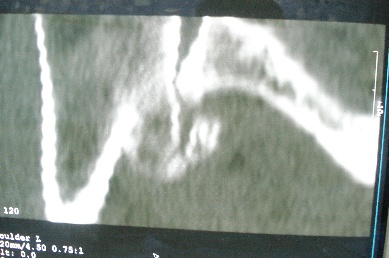

右上肢活动不便多年,最近加重。右肱骨肿瘤,请会诊!

骨软骨瘤恶变可能性大

右肱骨近断骨软骨瘤伴临近关节退变.有无恶变建议进一步检查.

右肱骨近断骨软骨瘤伴临近关节退变。

病变边缘轮廓清晰无骨质破坏,邻近软组织不肿胀,不支持肿瘤恶变。